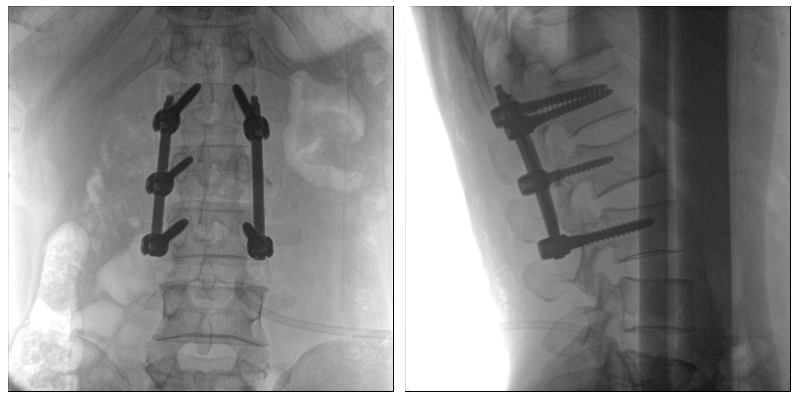

從下圖中可以看到二維影像能夠提供目標區(qū)域在某一個平面的重疊影像,雖然因為人體不同組織的密度差異,使得圖像具有較為豐富的信息量,但組織間的相互重疊還是會出現(xiàn),諸如空間位置等眾多信息在影像中遺失或不可辨認的情況,影響了醫(yī)生對信息的收集與應(yīng)用。

術(shù)中二維影像